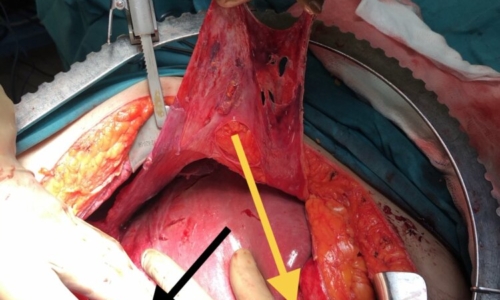

7 SAAT SÜREN YUMURTALIK KANSERİ AMELİYATI İLE HASTAMIZIN KARNINDAN 8 LİTRE SIVI BOŞALTILDI VE GERİDE KANSER KALMADI

YUMURTALIK (OVER) KANSERİ Yumurtalık (over) kanseri, kadınlarda en sık ölüme neden olan jinekolojik kanserdir. En sık 50 yaş…